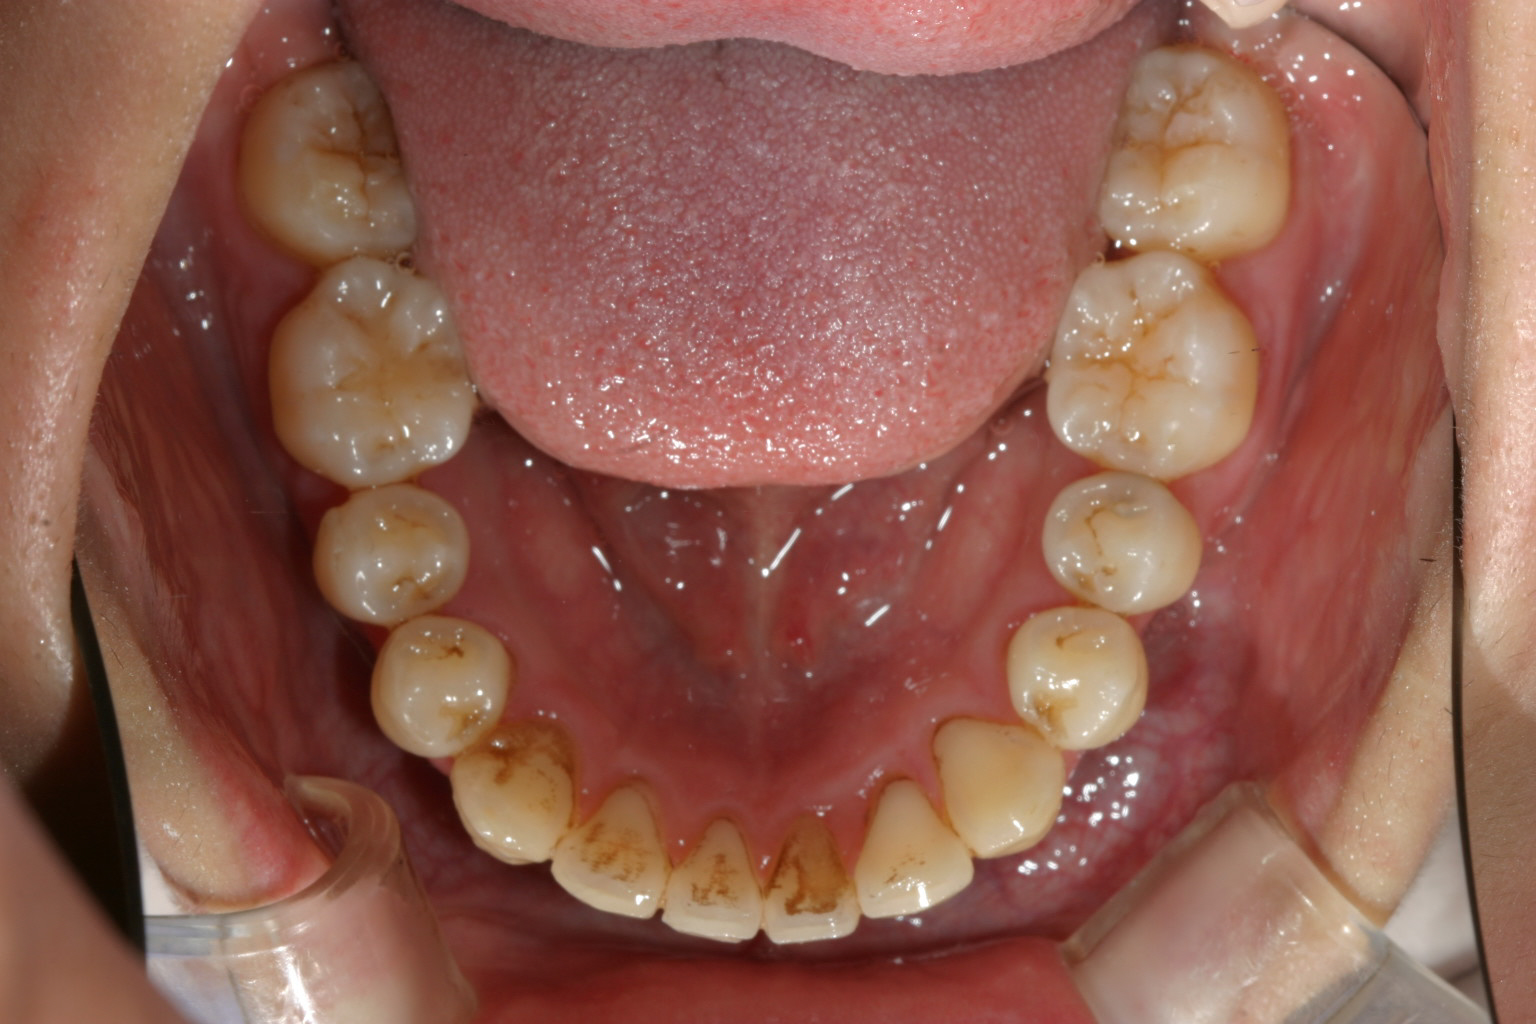

下顎前歯の叢生もかなりのもんです。 と言う事でワイヤー矯正を選択しました。

下顎のアーチも綺麗です。